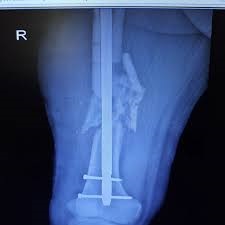

رادیوگرافی ساده: نشان‌دهنده فاصله بین قطعات استخوان و وضعیت جوش خوردن است.

سی‌تی اسکن: جزئیات بیشتری از بافت استخوان و محل جوش نخوردن ارائه می‌دهد و به جراح در برنامه‌ریزی جراحی کمک می‌کند.

جراحی تثبیت استخوان

در این روش، قطعات استخوان با پیچ، پلاک یا میله‌های داخل استخوانی تثبیت می‌شوند تا موقعیت صحیح حفظ شود و جوش خوردن سریع‌ترانجام گیرد. انتخاب روش جراحی و نوع وسایل فلزی بستگی به وضعیت استخوان دارد.